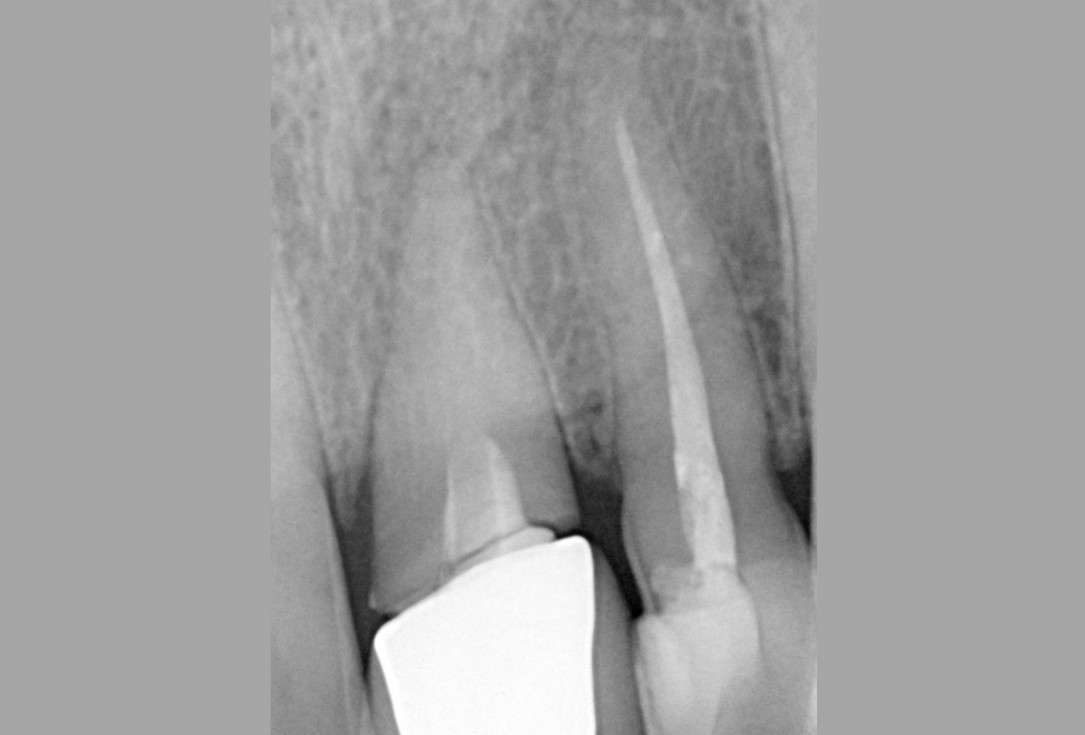

06/16 - X-ray control after filling of socket